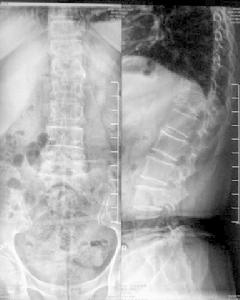

3、X線檢查 主要改變為皮質變薄,骨小梁減少變細,以脊椎和骨盆較明顯,特別是自胸腰段負重節段。早期見骨密度減低,透明度加大,水平方向的骨小梁吸收變細、少、分支消失,沿應力線保存的稀疏骨小梁呈垂直的柵狀排列。一般當X線中呈現改變時,骨礦物質的減少已在30%~50%以上。至後期縱行骨小梁也被吸收,抗壓能力明顯減退。海綿疏鬆骨較緻密骨更易脫鈣,故椎體受椎間盤壓迫而形成雙面凹陷,也可見脊椎壓縮性骨折或其他部位的病理骨折。X線上有時不易和軟骨病區別,特別在二者同時並存時。現可通過骨密度儀來診斷和估計骨質疏鬆的程度,如X線二重能量吸收測量術(X-ray-based dual-energy absorptiometry,DEXA)等 。

根據臨床表現及必要的內分泌機能測定,尿羥脯氨酸及骨骼X線檢查,DEXA檢測,臨床上雖可見單純的骨質疏鬆,亦常見本症和骨軟化同時存在。